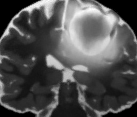

V-C Non-Registered MRI Segmentation Experiments

To demonstrate the robustness of the superpatch structure and the proposed framework, we apply SPM to brain tumor segmentation on multi-modal non-registered Magnetic Resonance Images (MRI). Classical patch-based and multi-atlas structure segmentation methods are based on registered subjects. Consequently, they cannot be efficiently applied in this non-registered context, due to the substantial variation in tumor shape and locations. Superpixels enable to better capture the tumor geometry, thus increasing the segmentation accuracy. Superpixel and supervoxel-based approaches have been applied to tumor segmentation [54]. However, in this work, the neighborhood is not considered and the ANN search is exhaustive, and computed on a large multi-modal histogram descriptor, leading to prohibitive computational time.

SPM can be efficiently applied to tumor segmentation since it quickly finds good correspondences without image registration, and uses the superpixel neighborhood to improve the matching. In this application, the segmentation is computed from a superpixel decomposition [1], then each region (tumor or background) is labeled with SPM.

We present results obtained on the MICCAI multi-modal Brain Tumor Segmentation (BRATS) dataset [49]. This challenging dataset contains real and simulated patient data, with overall poor resolution and large variation of tumor shape and position. For both types, high grade (HG) and low grade (LG) tumors are provided with four modalities: T1, contrast enhanced T1 (T1C), T2, and FLAIR. Overall, there are 20 and 10 real patient data with respectively HG and LG tumors, and 25 images for both HG and LG simulated tumor data. We use the same SPM parameters as in Section V-B, taking a multi-modal histogram, containing the levels of gray intensity on all MRI modalities as descriptor for superpatch matching, and performing the regularization (8) at the pixel scale to compare with pixel-wise ground truths. Each subject is segmented by the remaining of its type in a leave-one-out procedure.

In Fig. 12, we show several tumor segmentation results for all data types.

In Table II, we compare results obtained using different descriptor structures:

patch-based [48], superpixel-based [54],

and superpatch-based (= pixels).

We use the Dice coefficient [55] as evaluation metric,

measuring the overlap between the automatically segmented structure and the ground truth.

The superpixel-based approach

appears very limited since it fails at capturing the tumor context and their location in other images.

Regular patches are also limited in this context, due to the variations in the structure shapes.

Superpatches provide a robust descriptor, since they follow image intensities and capture the superpixel neighborhood,

leading to more accurate segmentation.

These experiments demonstrate that superpatches within the SPM framework provide fast and accurate segmentation results

even on non-registered multi-modal images with poor resolution.